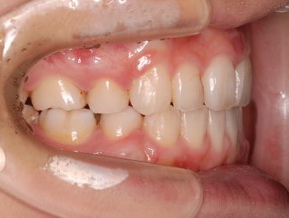

上顎の劣成長 (成長不足) による反対咬合で、上顎は拡大装置と上顎前方牽引装置を併用し前方方向への成長を促して前歯の咬み合わせを改善した後に、上下顎の前歯をマルチブラケット装置で並べました。治療の期間は2年でした。

初診時

1期治療終了時

2期治療終了時